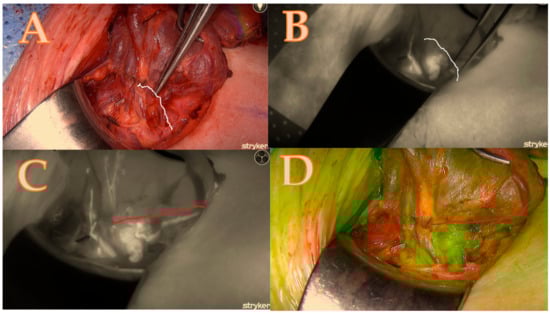

- The score ratio is calculated by dividing the total score by the maximum possible score and converting it into a percentage. In this case, 11/14 = 78.5%. This methodology allows for a comprehensive and standardized assessment of parathyroid gland viability, combining clinical assessment with advanced fluorescence imaging (see Table 1 and Figure 1, Figure 2, Figure 3 and Figure 4).

Table 1. The calculated score of the Burjeel ICG scoring technique, which corresponds to Figure 4. NA means not applicable.

Figure 4. Right upper parathyroid; (A) = native image, (B) = the maximum brightness of the ICG illustration in black-and-white mode, (C) = the maximum brightness of the ICG illustration in coloured mode, (D) = the maximum brightness of the ICG illustration in green mode; a total score of 4/7.